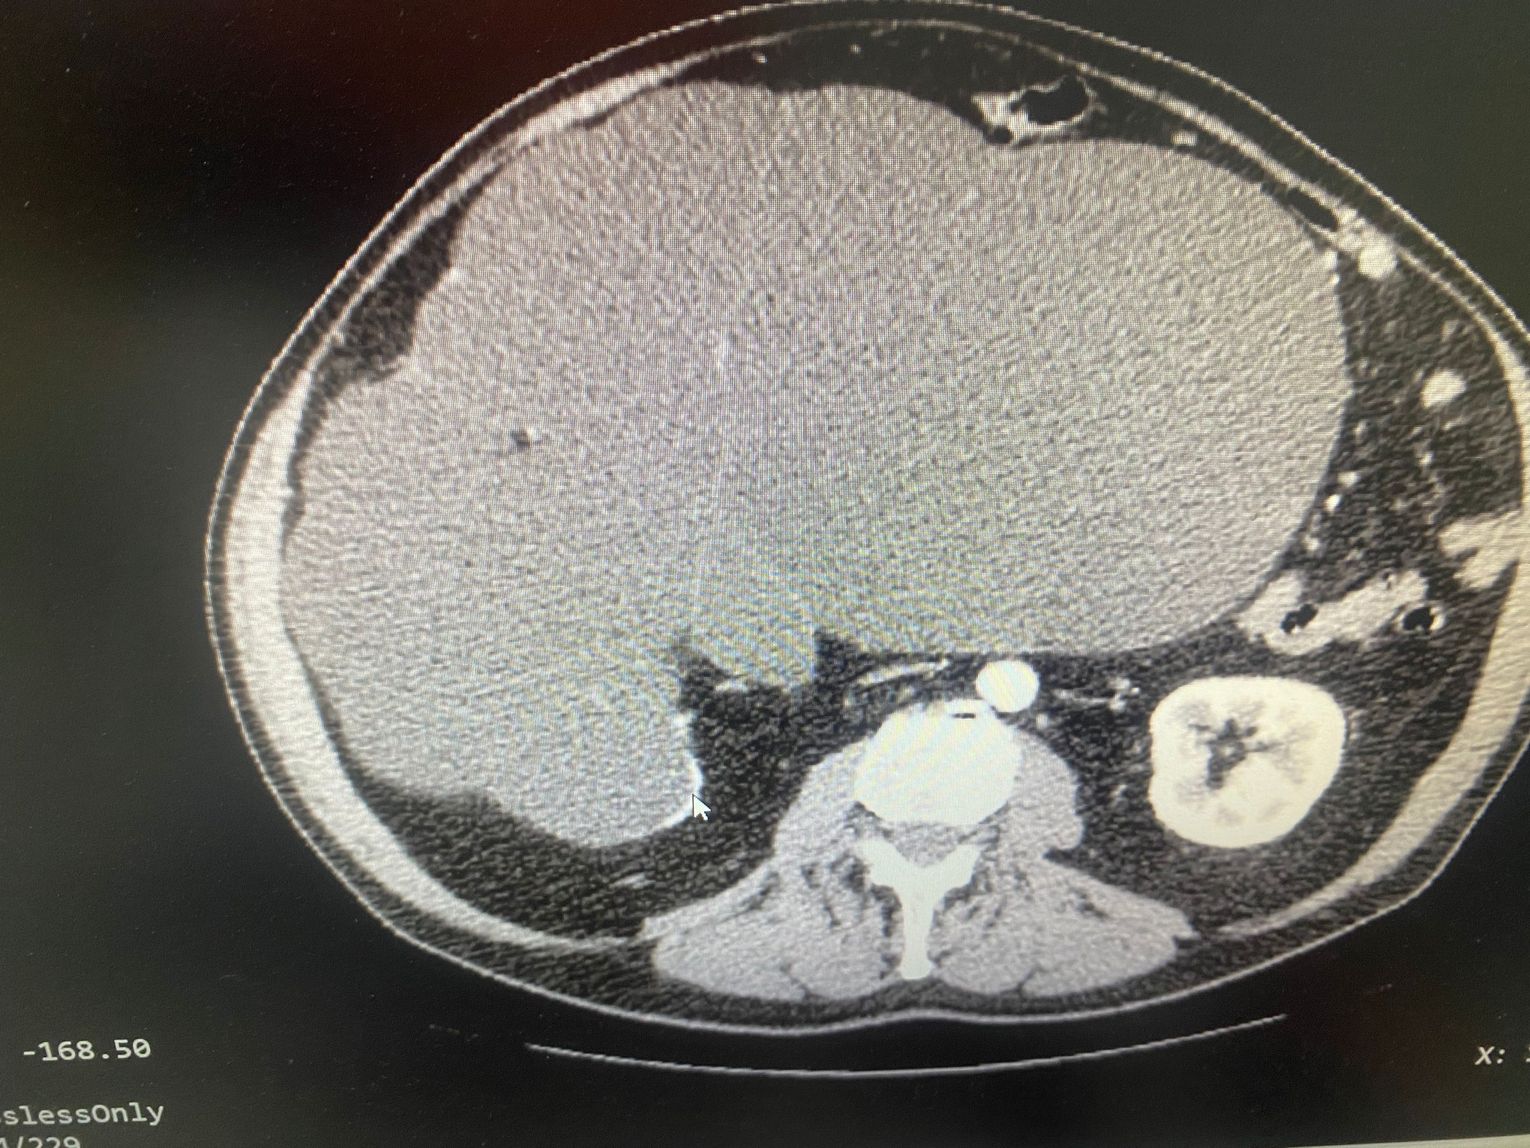

Pierwszy z pacjentów, to blisko 70-letni mężczyzna. Od lat walczył z otyłością, lecz mimo wielu prób nie udawało mu się jej pokonać. Zgłosił się do lekarza i dopiero w pogłębionej diagnostyce przeprowadzonej w kozielskiej lecznicy wykryto rozległą patologiczną zmianę w obrębie nerki. Guz utrudniał już znacznie normalne funkcjonowanie spychając pozostałe narządy w jamie brzusznej. Podjęto decyzję o natychmiastowej operacji metodą nie laparoskopową, a klasyczną, z uwagi na objętość i charakter umiejscowienia zmiany. Po 2,5-godzinnej operacji usunięto zmianę, której dokładne badania przeprowadzają obecnie histopatolodzy. Lekarze wstępnie określili zmianę jako wodonerczowo-guzowatą. Warto dodać, że objętość tego ogromnego guza to ok. 13 litrów, przy poprawnej objętości nerki ok. 300~500 ml. Zabieg zakończył się sukcesem, a pacjent czuje się bardzo dobrze i obecnie nie wymaga już leków przeciwbólowych.